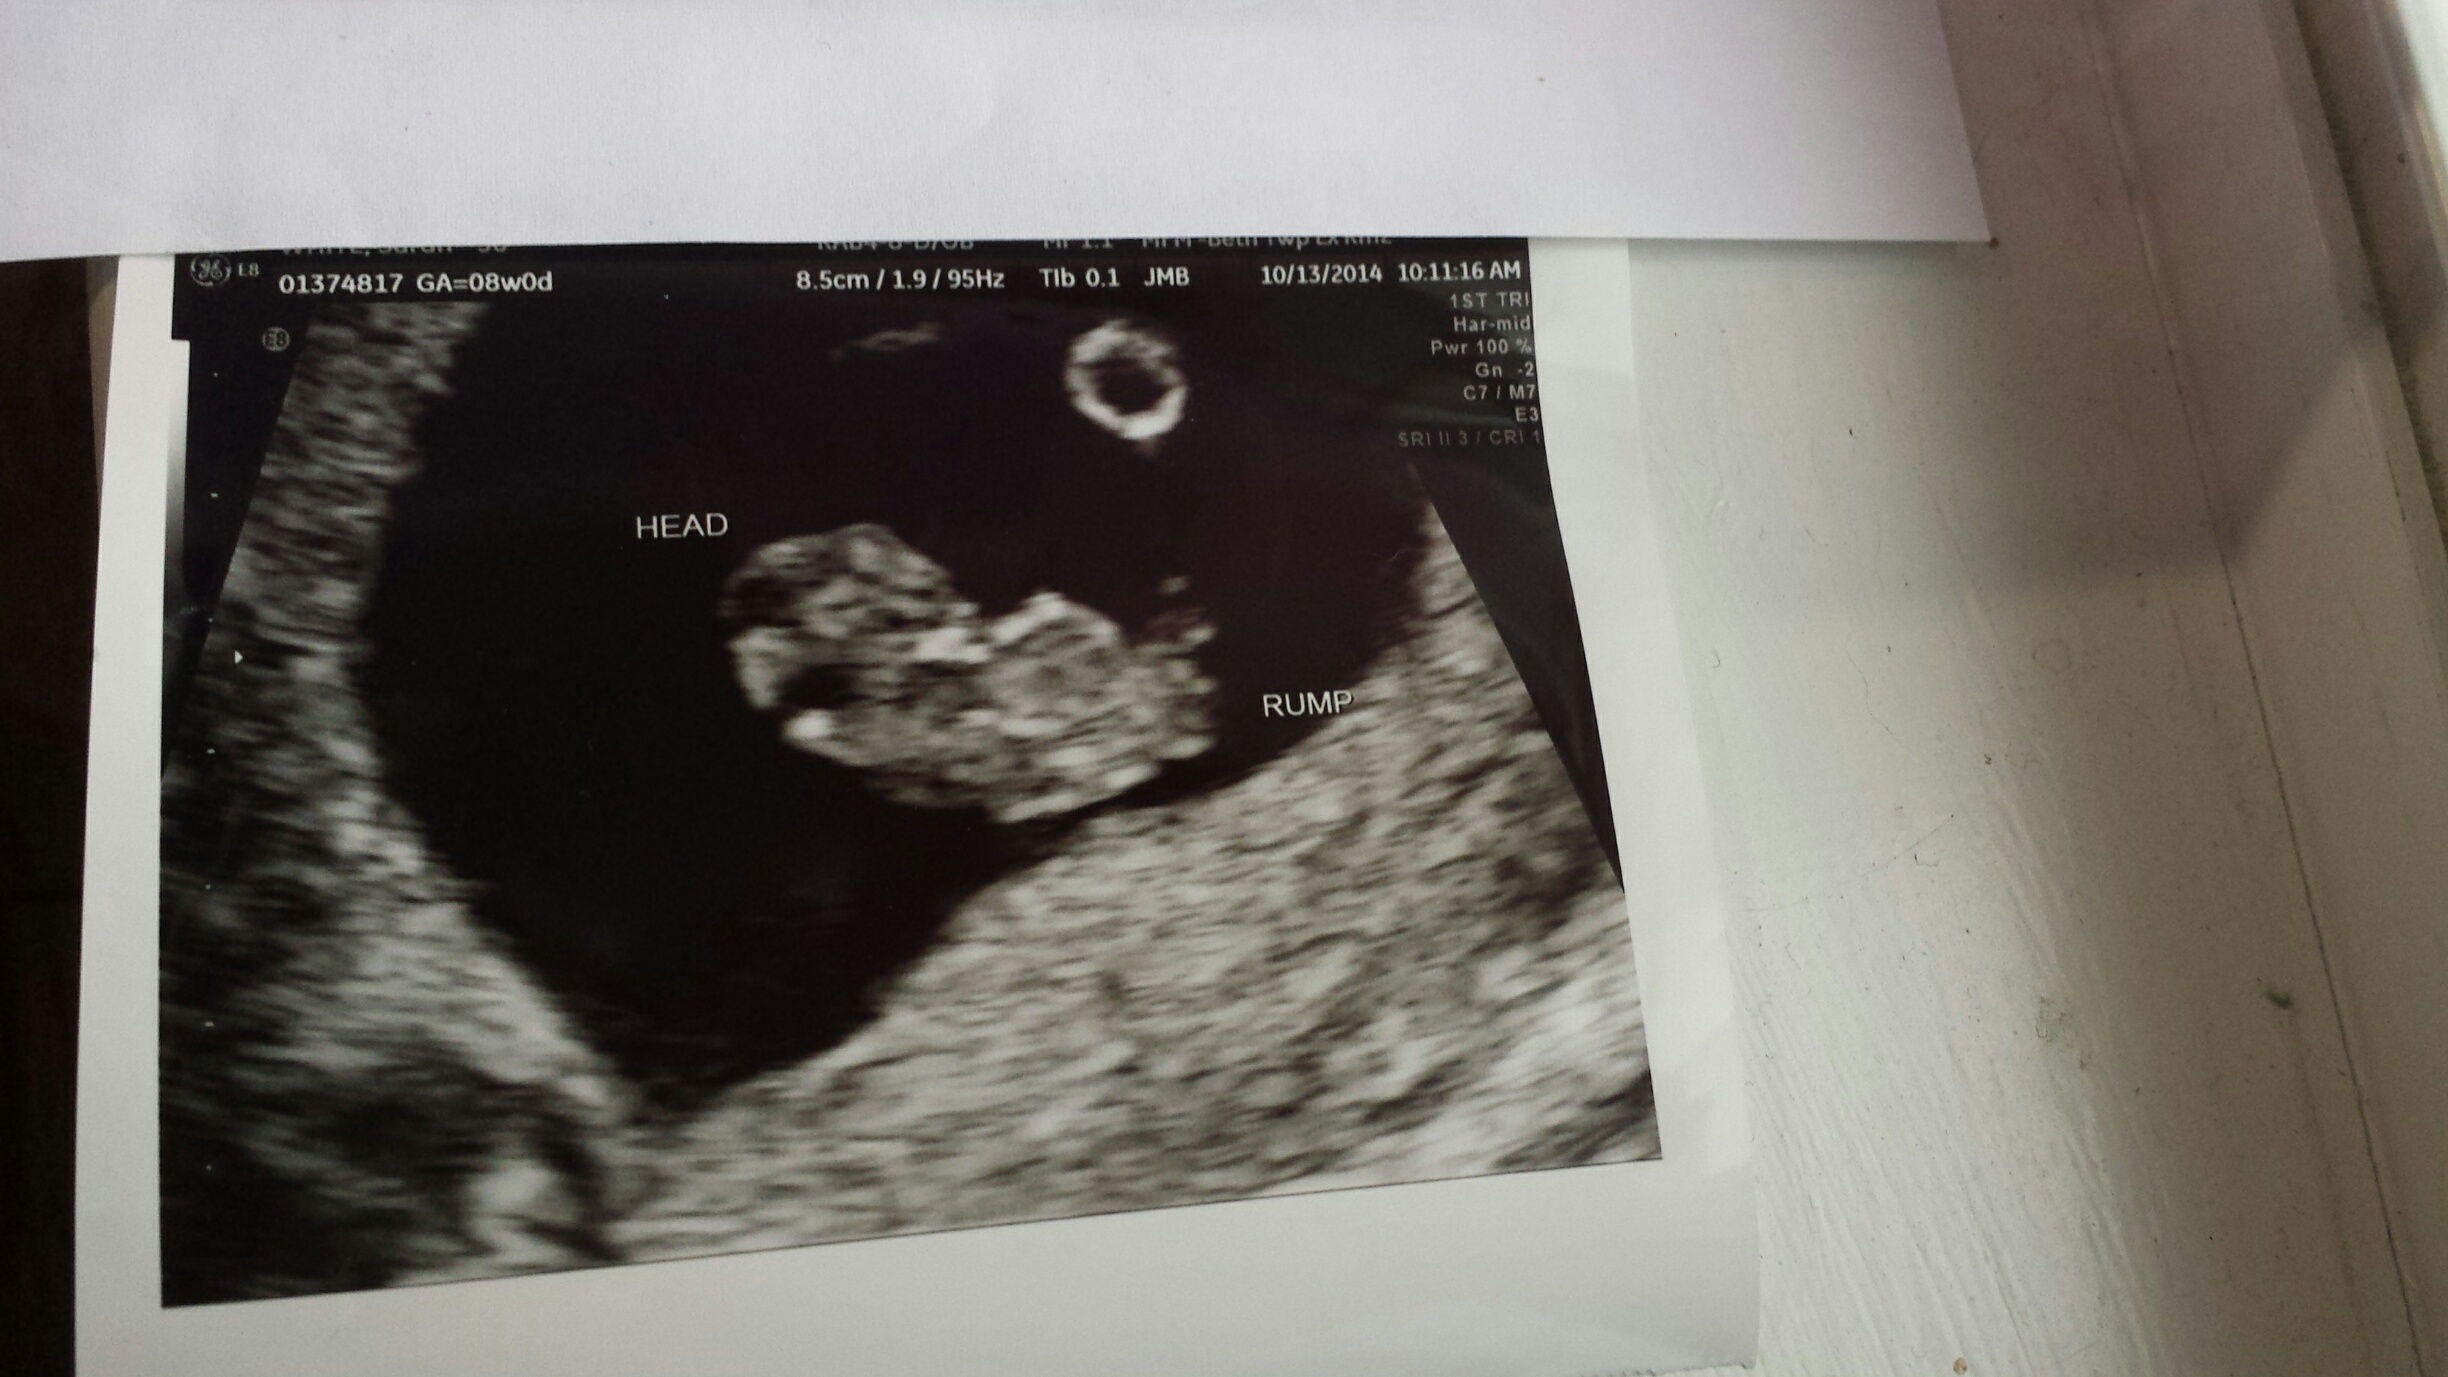

I had my abdominal ultrasound this morning. I was told that I am 8 weeks 4 days pregnant. Any guesses?

I was told the yolk sac was the circle in the picture. I would have asked for a closer picture. Oh well too late now.